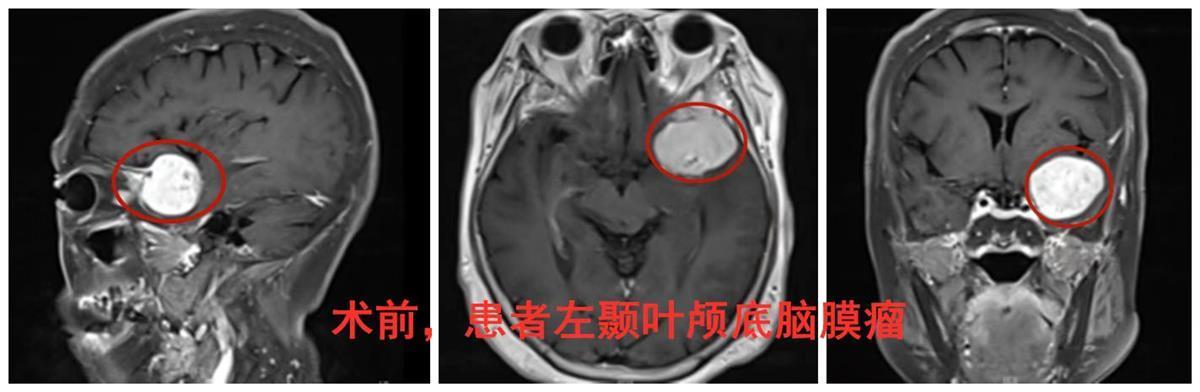

术前影像图

经完善系统检查,老人被查出左脑颞部有一个直径达4公分的脑膜瘤,结合发病症状及检查结果,接诊的脑肿瘤专家岑波教授表示,高婆婆娱乐时出现的反应迟钝、记忆力下降、发呆愣神等表现,正是由于脑膜瘤占位继发了症状性癫痫所致。当务之急是要尽快切除脑瘤,给神经组织减压。